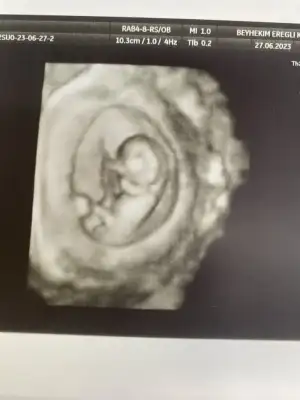

Merhaba 11 haftalık hamileyim bende bir aksilik olmazsa Aralık sonu ile 13 Ocak'a kadar doğum bekliyorum :) Biz cinsiyetini hala sormadık ve öğrenmedik bir süre daha öğrenmeyi düşünmüyorum, eskiden hep kız çocuk isterdim ama nedense oğlum olduğunu hissediyorum,